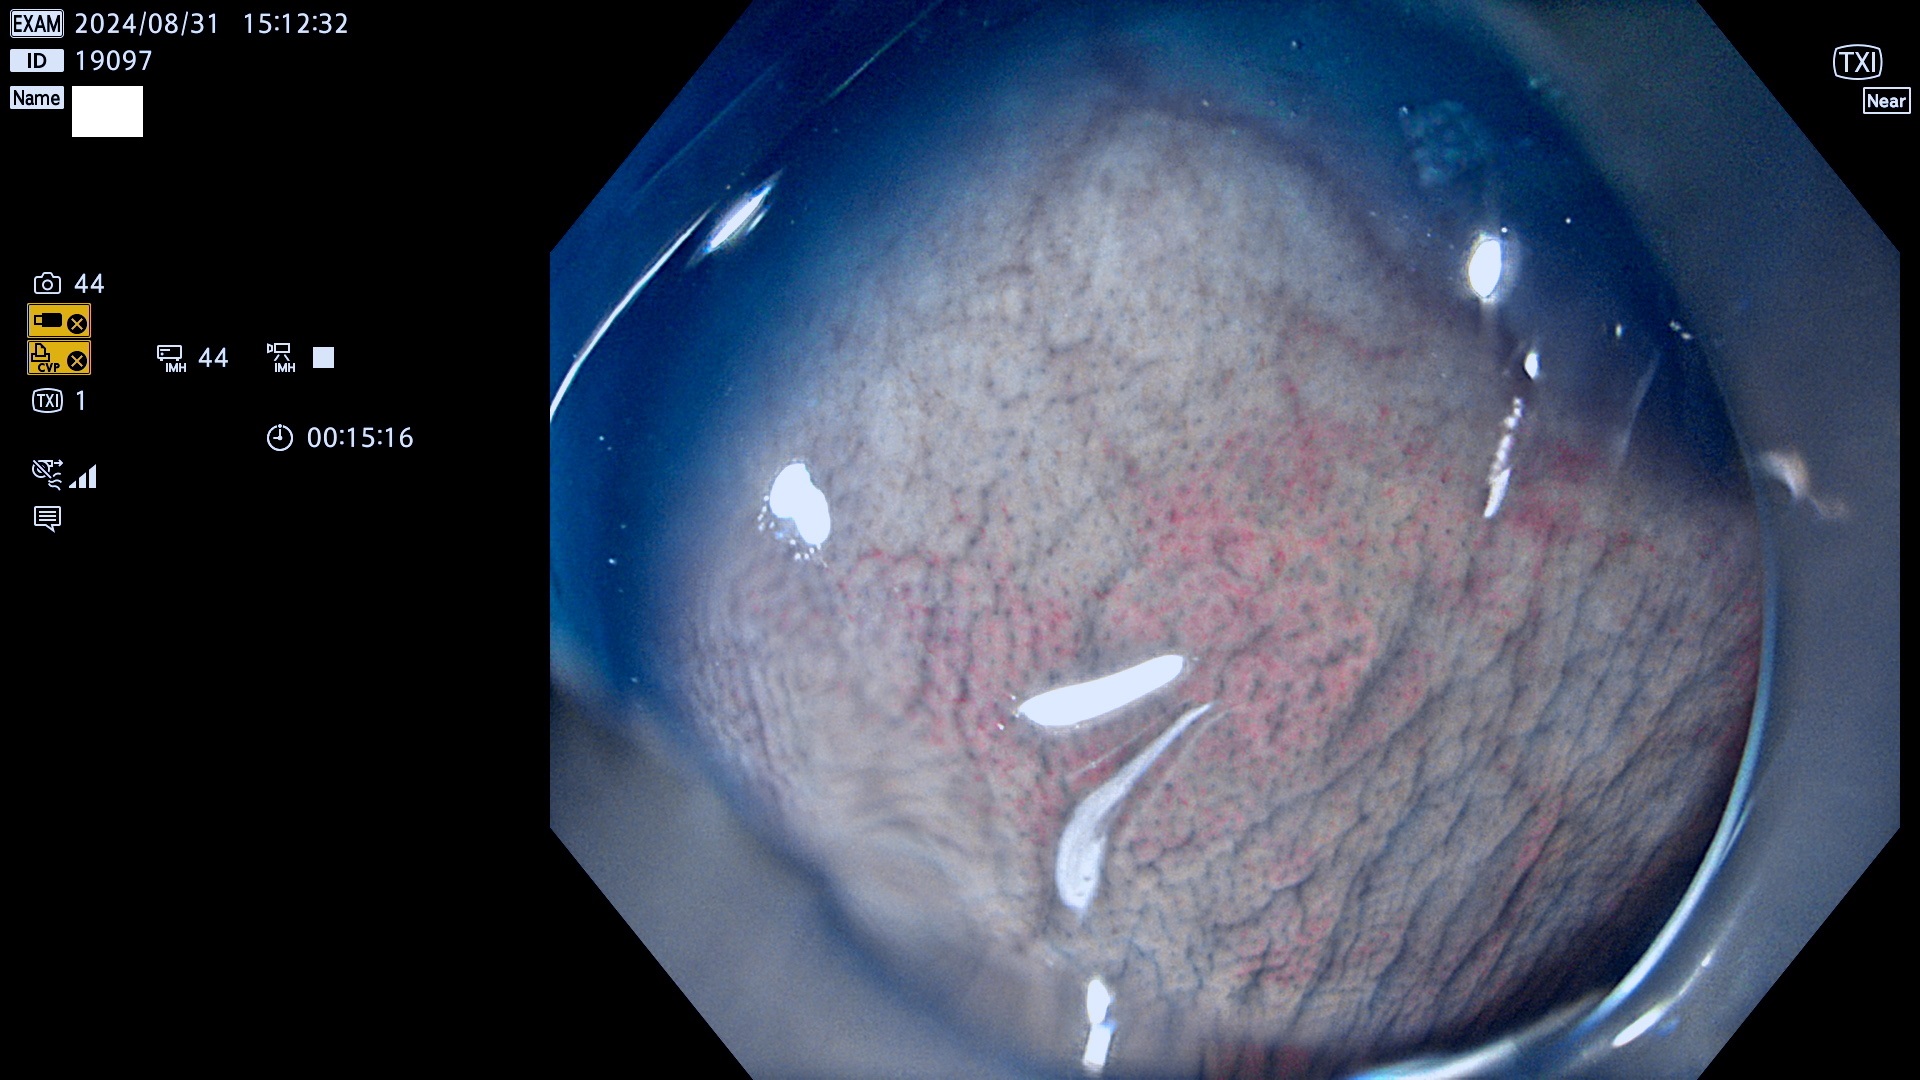

完全に平坦な物をUb、陥凹している物をUcと呼びます。最も発見が難しく危険な病変です。

抽出の対象期間 2024年8月29日〜9月1の4日間(40件の検査)5件 (5/40=13%)